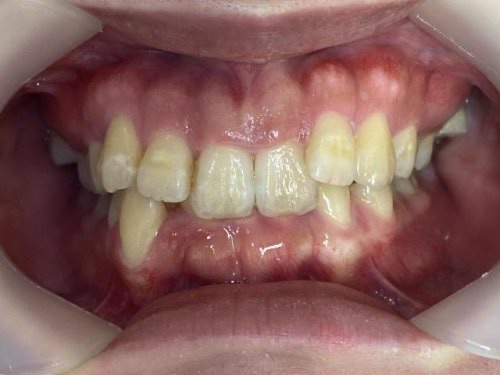

20代女性「咬み込みが深くてうまく笑えない」上の歯が下の歯に覆いかぶさった「過蓋咬合」を、歯を抜かずにマウスピース型矯正装置「インビザラインフル」で正しい咬み合わせに改善した症例

「咬み込みが深い。前歯の歯茎が見えすぎてうまく笑えない」と、ご相談いただきました。

拝見したところ、上の歯が下の歯に覆いかぶさって深く咬み込んでいる「過蓋咬合(かがいこうごう)」でした。

奥歯(第1大臼歯/6番)の咬み合わせで判断する「アングルの分類」では、上の歯が前方に出ていて、さらに内側に傾斜して生えている「アングルⅡ級2類」と診断しました。

また、全体的に歯が黄ばんでいて、口元が暗い印象でした。